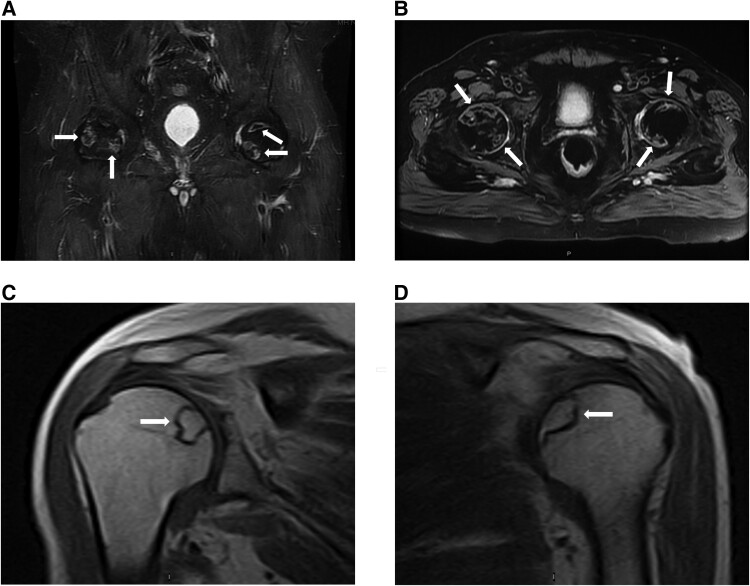

库欣综合征(CS)是由于长期暴露于过量的糖皮质激素,导致一系列临床表现,包括无血管坏死(AVN),一种罕见的CS并发症。虽然AVN通常与外源性糖皮质激素治疗有关,但它也可能发生在内源性CS中,但由于其罕见性和可能的亚临床表现而未被识别。我们描述了一例71岁的男性库欣病患者,他最初表现为双侧髋关节AVN,后来发展为双侧肩部AVN,尽管经蝶窦手术和辅助立体定向光子放射治疗后生化缓解。内源性CS中AVN的报道不足,缺乏常规筛查的指导。我们的病例强调了在CS患者中考虑AVN的重要性,特别是那些持续或反复出现关节症状且皮质醇水平明显升高的患者。早期发现AVN是至关重要的,因为如果不治疗,它可能导致不可逆转的关节损伤和残疾。应探索筛查策略,识别诊断为CS的高危患者,及时干预,从而预防AVN相关的长期发病。

Cushing syndrome (CS) results from prolonged exposure to excess glucocorticoids, leading to a range of clinical manifestations including avascular necrosis (AVN), a rare complication of CS. Although AVN is often associated with exogenous glucocorticoid treatment, it can occur in endogenous CS but may be unrecognized because of its rarity and possibly from a subclinical presentation. We describe a case of a 71-year-old male with florid Cushing disease who initially presented with bilateral hip AVN and later developed bilateral shoulder AVN despite achieving biochemical remission following transsphenoidal surgery and adjuvant stereotactic photon radiosurgery. AVN in endogenous CS is underreported, and guidance on routine screening is lacking. Our case underscores the importance of considering AVN in patients with CS, especially in those with persistent or recurrent joint symptoms and markedly elevated cortisol levels. Early detection of AVN is crucial as it can lead to irreversible joint damage and disability if untreated. Screening strategies should be explored to identify high-risk patients who are diagnosed with CS for timely intervention, thereby preventing long-term morbidity associated with AVN.